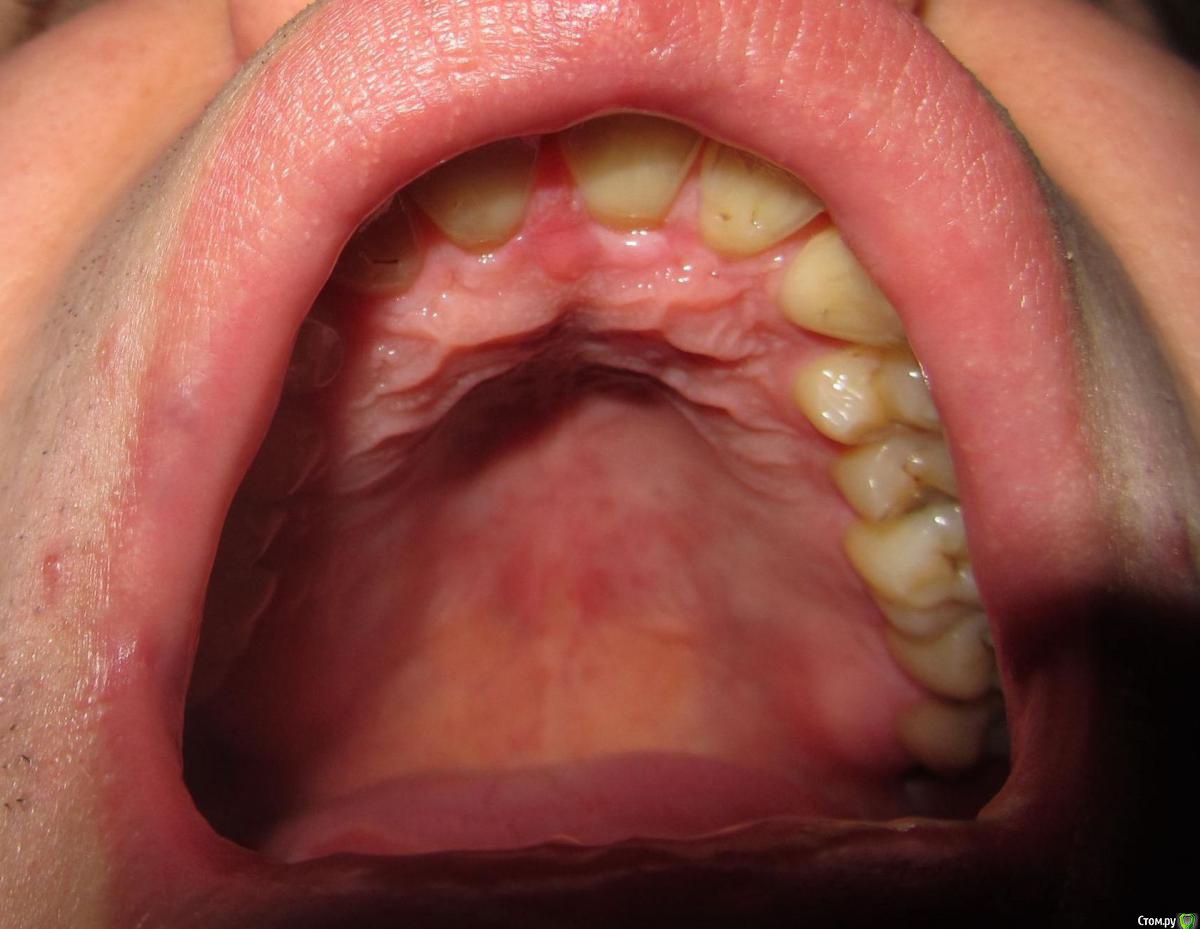

janis1 Опубликовано 14 ноября, 2015 Поделиться Опубликовано 14 ноября, 2015 Доброго времени суток, уважаемые профессионалы.Очень надеюсь на вашу помощь.Коротко о себе:37 лет, пол мужской. Так сложилось что в последнее время меня постигло сразу три проблемы,как мне кажется все они имеют между собой четкую связь. Основная проблема, с болями верхней челюсти, началась у меня около месяца назад. Боль не очень сильная, но практически постоянная. Боль не имеет какой-либо конкретной локации (болит именно вся челюсть). С утра она меньше, ближе к вечеру усиливается. В последнее время немного отдаёт в скулу. Одновременно с появлением боли, во рту, в районе дёсен, появился как бы привкус соды (немного похожий на вкус крови, но крови в ротовой полости нет).И в довершение всего начали катастрофически искривляются зубы верхней челюсти.На самом деле проблемы с прикусом у меня были уже с детства, примерно в 10 - 12 лет я носил пластинку для исправления прикуса.Но к сожалению лечение так и не закончил, соответственно прикус все это время у меня был неправильным, но до последнего времени он меня не беспокоил, так как был если так можно сказать "в пределах разумного", и в течении долгого времени был неизменен, но в последние несколько месяцев верхние зубы искривились настолько катастрофически что что я реально начал шепелявить. При попытке расшатывания зубы стоят крепко, не болтаются. Пока во всяком случае... Со всеми этими проблемами я пробовал обращаться к зубному хирургу и ортодонту,ни хирург, ни ортодонт к которым я обращался не смогли назвать каких-либо конкретных причин по которым может появляться боль в верхней челюсти и привкус во рту.Врачи к которям я обращался действительно хорошие специалисты, но похоже видят проблемы узко по своей специализации.Единственно хирург указал на то, что возможно придется удалять восьмерки, а ортодонт предложил установить брекеты на обе челюсти.Я прекрасно понимаю что с таким прикусом мне действительно не избежать установки брекетов, но меня беспокоит то, что не найдена причина происхождения всех проблем о которых я написал. Очень надеюсь на вашу помощь в поиске возможных причин проявления моих проблем. Заранее благодарен! Ссылка на комментарий

Jurai Опубликовано 22 ноября, 2015 Поделиться Опубликовано 22 ноября, 2015 Есть проблема во фронтальном участке верхней челюсти: общая убыль костной ткани, ячеистая структура кости. смещение зубов так, что корни изогнулись, это значит, что либо резорбция (рассасывание) либо очень длительное уже идет воздействие. Могу подозревать новооборазование в этом участке.Вам нужна консультация челюстно-лицевого хирурга-онколога. 1 Ссылка на комментарий